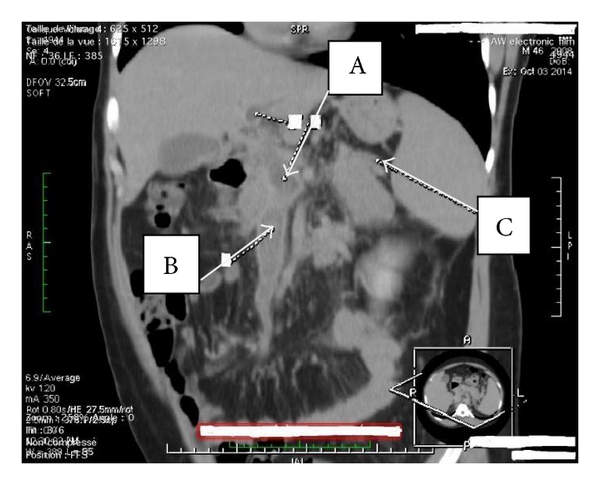

A 46-year-old Cameroonian man, living in North Cameroon, was admitted to the Yaoundé University Teaching Hospital for diffuse abdominal pain accompanied by abdominal distension and vomiting for three-week duration. This was treated as a gastroduodenal ulcer without accurate diagnosis on endoscopy. His past medical history was unremarkable. The physical exam revealed a distended and tympanic abdomen, diffusely tender with no guarding. There was no palpable mass and bowel sounds were present. The digital rectal exam elicited pains on both sides. On admission, he has a low grade fever with a temperature of 38.2°C; the blood pressure was 113/82 mm Hg, and the heart rate 102 beats/minute. The laboratory tests (hemogram and biochemistry) were normal except for a C-reactive protein of 160 mg/L (standards: less than 6 mg/L), the lipase of 6xULN (upper limit of normal), and mild hepatic cytolysis (ALT greater than 3xULN). The tests of the hepatitis B surface antigen, the anti-hepatitis C virus antibodies, and the human immunodeficiency virus (HIV) were negative. Abdominal Doppler ultrasonography revealed an extensive venous thrombosis of the portal, splenic, and mesenteric veins (Figure 1). The abdominal contrast-enhanced CT scanner confirmed the extended thrombosis and highlighted an infiltration of the proximal pancreas associated with inflammatory flows in the peritoneum (Figure 2).

The diagnosis of necrotizing AP complicated by PSMVT was done. In the absence of significant contraindications factor, the patient received low molecular weight heparin (enoxaparin 1 mg/kg subcutaneously twice daily), followed by oral warfarin on the 10th day, dose adjusted according to the International Normalized Ratio (INR). The repeated abdominal Doppler ultrasound on the 12th day from admission showed a partial recanalization of the extensive venous thrombosis, confirmed by the abdominal contrast-enhanced CT scanner on 30th day which showed collateral vessels and small bowel edema (Figure 3). For accurate diagnosis, specific tests have shown normal serum lipids, and the tests for anti-nuclear antibodies, anti-native DNA antibodies, and antiphospholipids were negative; the hemoglobin electrophoresis was AA type. On the contrary, the functional test of protein C (STA Stachrom) showed a serum rate of 25% (normal range: 80–130%, Cerba Laboratories, France) and that of the protein S (STA Staclot) was 50% (normal range: 70–130%, Cerba Laboratories, France). Upper gastrointestinal endoscopy performed three months after follow-up showed grade II esophageal varices (Figure 4). There were no adverse effects on anticoagulation after three months of follow-up.

The combination of Doppler ultrasonography and CT scanner increases the diagnostic sensitivity. Doppler ultrasonography and CT scanner have a negative predictive value of 98% and 100%, respectively. Both tests enable showing pseudoaneurysm, intrapseudocystic bleeding, intra-abdominal collections, venous thrombosis, and varices [11, 12]. We performed both exams for diagnosis in this case.